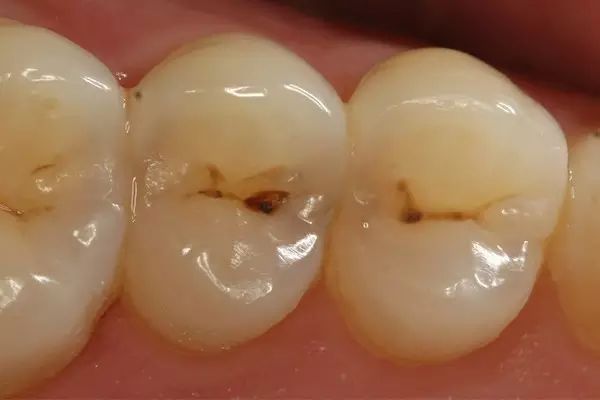

第一步:浅龋

当我们牙齿上有小黑点时,您毫不在意地说:“没事的,没感觉。”

牙医说:“龋病是由以细菌为主的多因素导致的牙齿硬组织发生慢性进行性破坏的一种疾病。已经开始浅龋即牙釉质龋,需要做药物治疗或充填治疗。